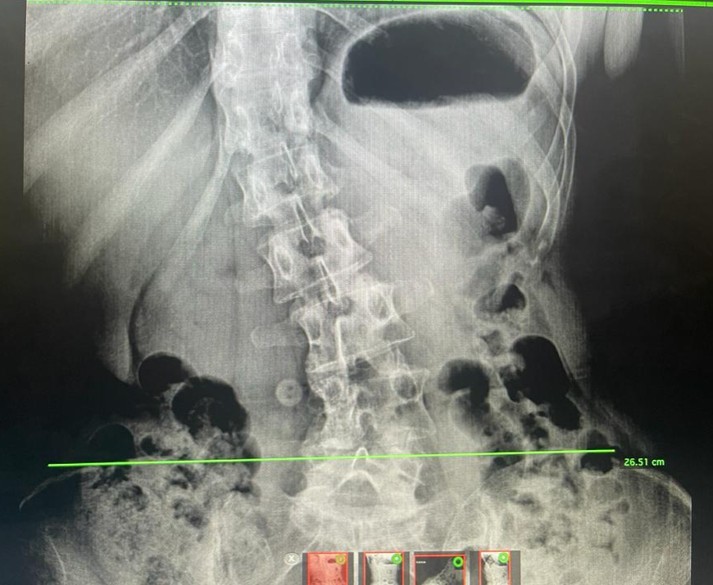

La escoliosis es una curvatura o desviación tridimensional de la columna vertebral, que puede ser leve en muchos casos, pero en otros, severa e incapacitante. En casos graves, puede requerir cirugías complejas de alta especialización. En ORTHO-SPINE-CENTER, ofrecemos tratamiento para la escoliosis tanto en adultos como en adolescentes.

El término «escoliosis» deriva del griego skolios, que significa «torcido». Por definición, la escoliosis se diagnostica cuando la desviación o curvatura de la columna supera los 10 grados. Si esta supera los 20 grados, es más común que se detecte a edades tempranas debido a asimetrías en las caderas o los hombros, así como deformidades en el tronco.

Tratamiento Quirúrgico de la Escoliosis (Enfoque General): La cirugía de escoliosis tiene como objetivo corregir el segmento curvado de la columna. Se realiza una realineación y fusión de las vértebras necesarias para fijar la columna en su nueva posición. Esto se logra mediante la colocación de tornillos transpediculares que se conectan entre sí con barras de metal para alinear y estabilizar la columna. En nuestro centro, aplicamos diversas técnicas quirúrgicas avanzadas para este procedimiento.